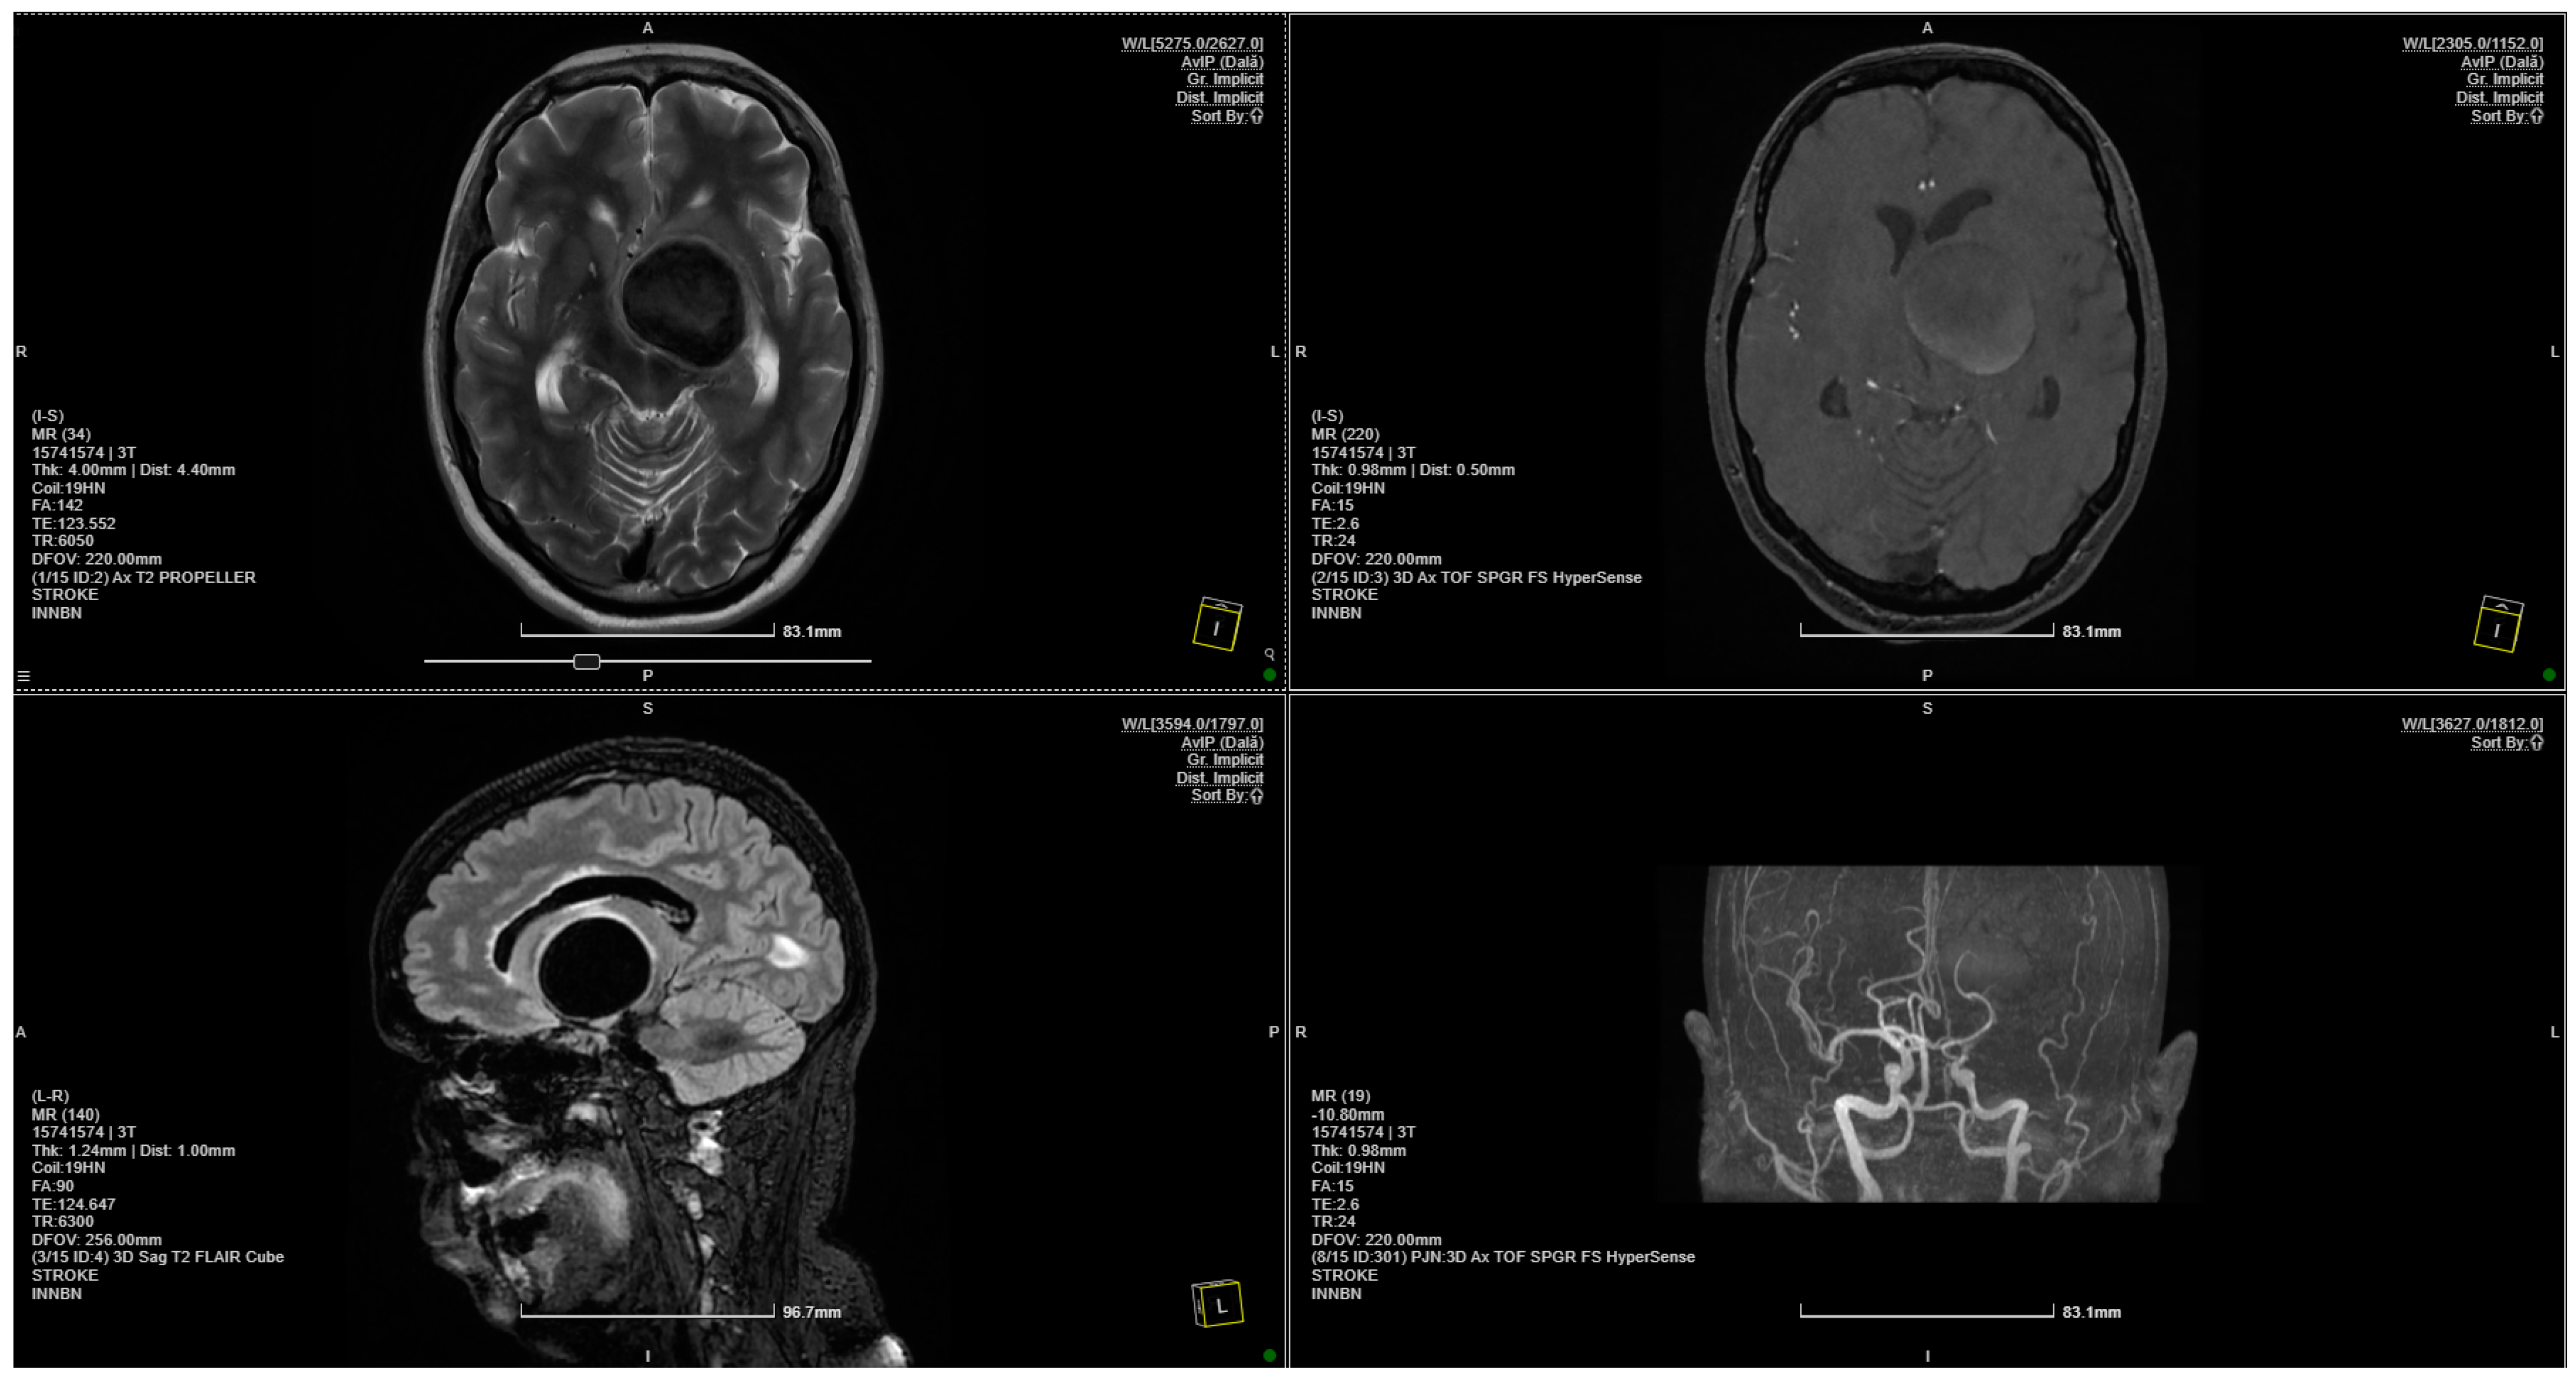

Figure 1.

MRI scan showing a 4 × 3.75 cm giant aneurysm.